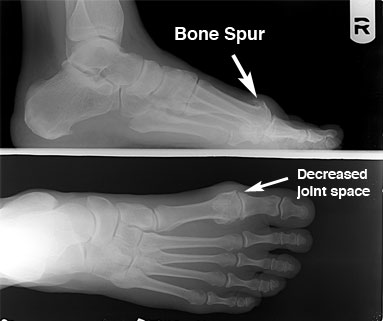

무지강직증이 만성화되면 만성적인 은은한 통증과 더불어, 골극(뼈조각)이 생겨 엄지발가락을 굽히고 펴는데 제한이 더 심해집니다. 또한 발의 통증이 아래다리, 무릎, 고관절, 허리에 영향을 미쳐서 무릎, 다리, 허리의 둔한 통증을 일으키고, 다리를 절뚝거리며 걷게 됩니다.

Grade 1: 30~40도 발등쪽으로 굽혀지고, 영상의학검사상 관절 공간이 약간 좁아져있고, 미세한 골극이 보인다. 약한 통증 및 강직이 동반됨

Grade 2: 10~30도 발등쪽으로 굽혀지고, 영상의학검사상 관절공간이 보통이상 좁아져있으며, 골극이 크게 보이고, 통증 및 강직이 강하게 나타나며, 최대 배측굴곡시 통증이 사라지지않고 지속된다.

Grade 3: 10도 이하로 발등쪽으로 굽혀지고, MP 관절낭의 변화가 보이며, 지속적인 통증 및 강직이 동반된다.

Grade 4: Grade 3와 같으며 추가로 midrange pain이 동반된다.